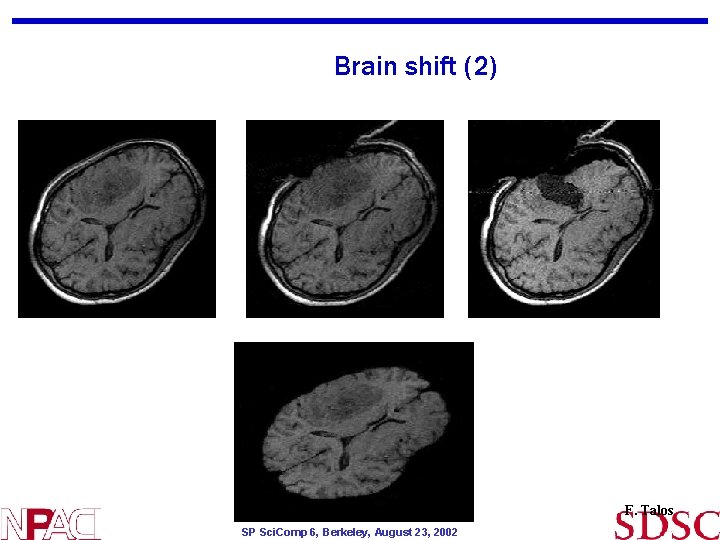

Brain shift (2) F. Talos SP Sci. Comp 6, Berkeley, August 23, 2002